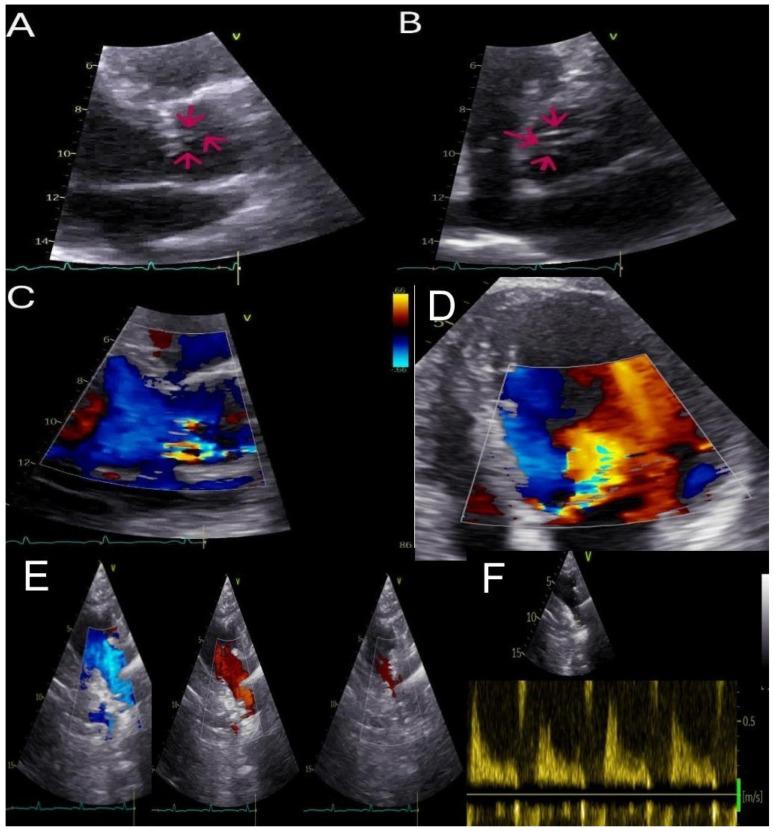

一例罕见的因腱索条索帐篷样改变继发严重主动脉瓣反流病例:一种用于具有挑战性诊断的多模态成像方法

We discuss a case of a patient who was referred to our department for an in-depth evaluation of aortic regurgitation severity and its underlying causes. By employing a multimodal imaging strategy that combined transthoracic echocardiography (TTE), transesophageal echocardiography (TEE), and cardiac magnetic resonance imaging (cMRI), we successfully identified a particularly rare cause of aortic regurgitation: chordae tendineae that lead to asymmetric retraction of the aortic cusps. Furthermore, this approach provided a clearer understanding of the aortic root anatomy and the hemodynamic effects of the regurgitant flow on the ventricle. This case demonstrates the diagnostic effectiveness of various imaging techniques and emphasizes the crucial importance of multimodal imaging for a thorough assessment of aortic valvular issues.

我们讨论了一例患者,该患者被转诊至我科,以深入评估主动脉瓣反流的严重程度及其潜在病因。通过采用一种多模态成像策略,该策略结合了经胸超声心动图(TTE)、经食管超声心动图(TEE)和心脏磁共振成像(cMRI),我们成功地确定了一种特别罕见的主动脉瓣反流病因:导致主动脉瓣叶不对称回缩的腱索。此外,这种方法能更清晰地了解主动脉根部解剖结构以及反流血流对心室的血流动力学影响。该病例展示了各种成像技术的诊断效果,并强调了多模态成像对于全面评估主动脉瓣问题的至关重要性。